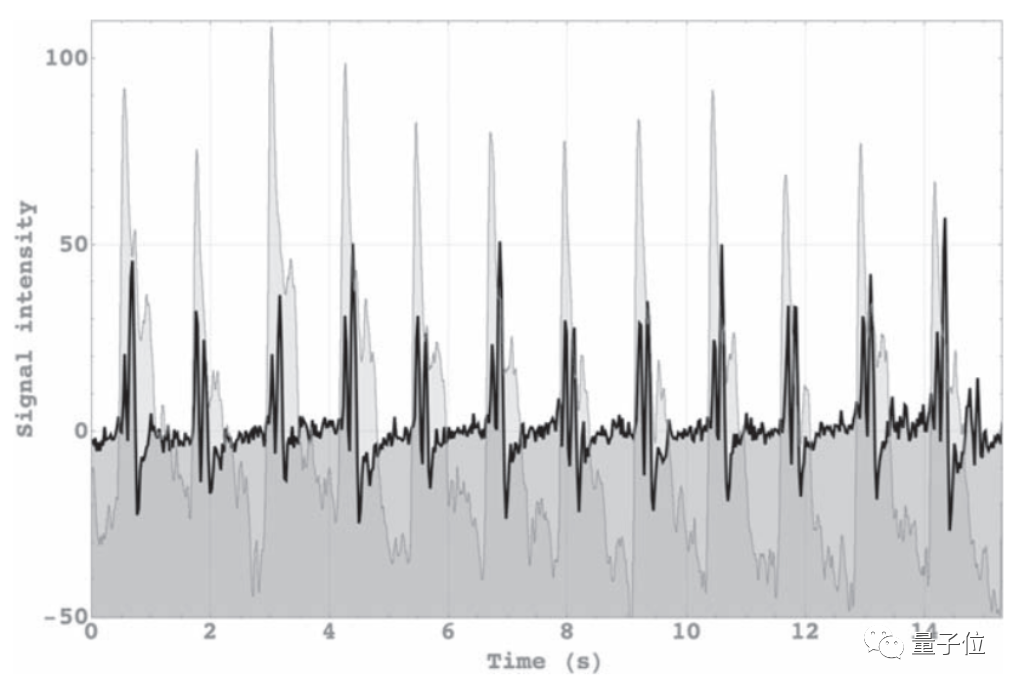

通过这种方法,在测量了40个人(18~46岁之间)的大脑信号后,研究人员在大部分人的大脑区域中都测量出了一种诱发脑电信号。

这类信号有点像心跳诱发脑电位信号(HEPs,大脑感应心跳的信号),都依赖于大脑意识的产生,主要与短期记忆与意识感知相关。

然而正常来说,基于多量子相干的核磁共振根本没办法检测到诱发脑电信号,因为这些信号与任何经典的核磁共振信号都没有相关性。

对此研究人员推测,这一现象用量子纠缠解释是最合理的,进一步来说,这也意味着这些大脑功能与量子计算相关。